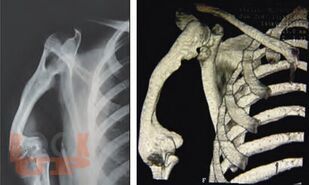

Ортопедические последствия гематогенного остеомиелита верхних конечностей у детей

Авторами представлен многолетний опыт лечения детей с ортопедическими последствиями гематогенного остеомиелита верхних конечностей. На основании комплексного обследования пациентов предложены оптимальные способы лечения детей с данной патологией.